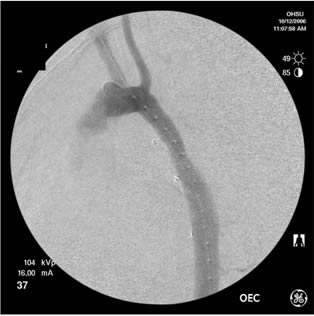

Selective angiography of the left subclavian artery was performed to confirm an intact posterior cerebral circulation. The proximal left subclavian artery was occluded with two 10mm Amplatzer vascular plugs which were introduced via the left external iliac sheath. An angiogram of the distal aortic arch and descending thoracic aorta was then performed to obtain a roadmap of the proximal and distal landing zones (Figure 4).